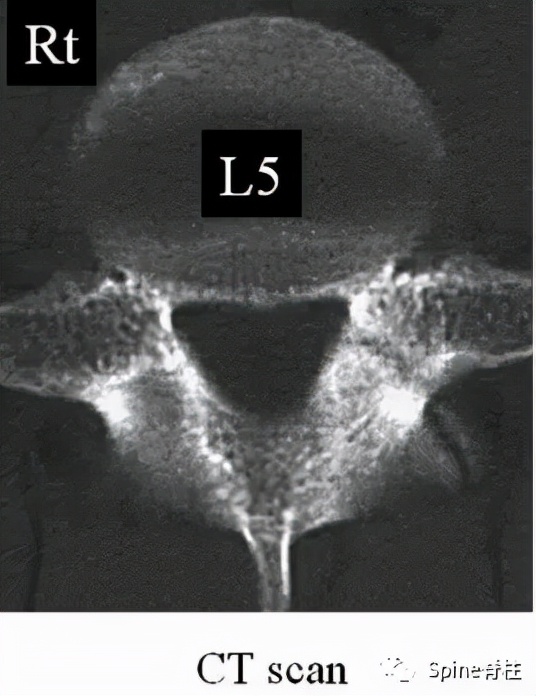

图:箭头所指为离断的椎体后缘

CT是诊断最有效的检查手段

图:A 型为分离部分含皮质骨,不伴椎体后方骨缺损(图A);B 型为分离部分较大,含皮质骨和松质骨,伴椎体后方较大骨缺损(图B);C 型为分离部分较小,含皮质骨和松质骨,伴椎体后方较小骨缺损(图C)。

由于对 腰椎椎体后缘离断症 (陈仲强)发生机理认识各异,有学者认为与青少年骺环未闭及运动创伤导致的椎体及骺环应力较大有关,也有学者认为是一种骨坏死,故命名尚未统一。

PARS 因与单纯 LDH 或 LSS 表现相似,临床易误诊或漏诊,并且 由于骨性致压因素的影响,PARS 患者的症状较单纯 LDH 严重 。对于经保守治疗无效,且存在神经根性症状或马尾神经损伤表现患者,应尽早手术治疗。